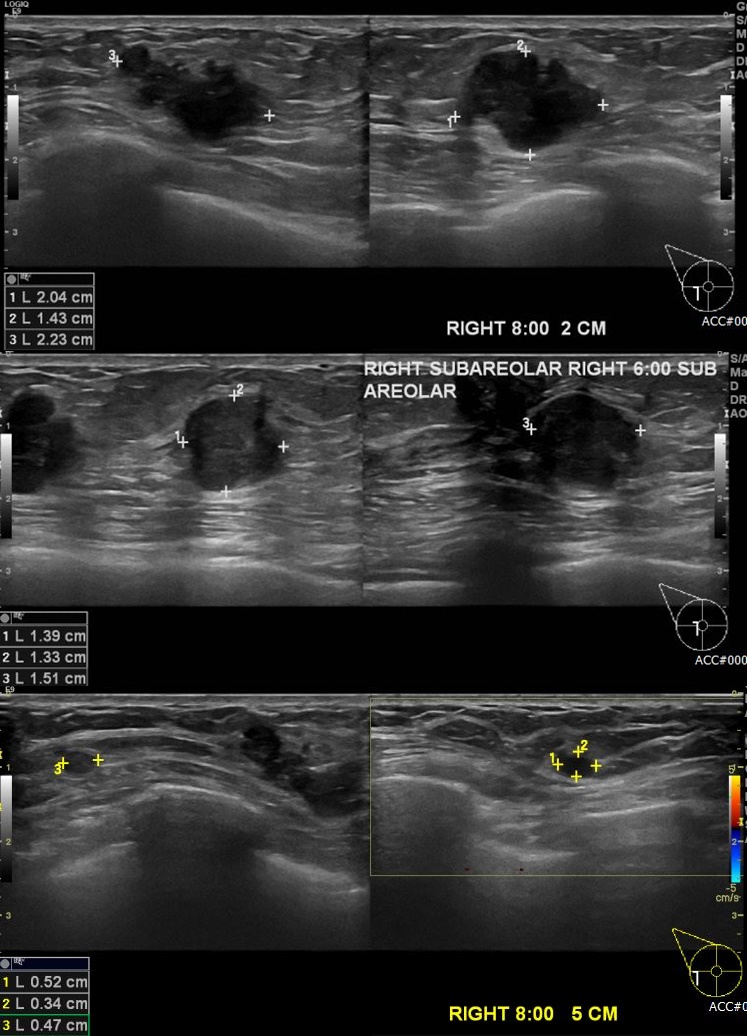

상기 환자 건강검진상 이상 소견으러 내원하신 60대 여성 분으로  우측 8시  방향  2cm,

5cm  거리의 혹 , 6시 방향 유륜 밑 의심스러운 혹 각각 조직검사 시행하여  조직검사 모두

우측 침윤성 유관암 진단 되었습니다.